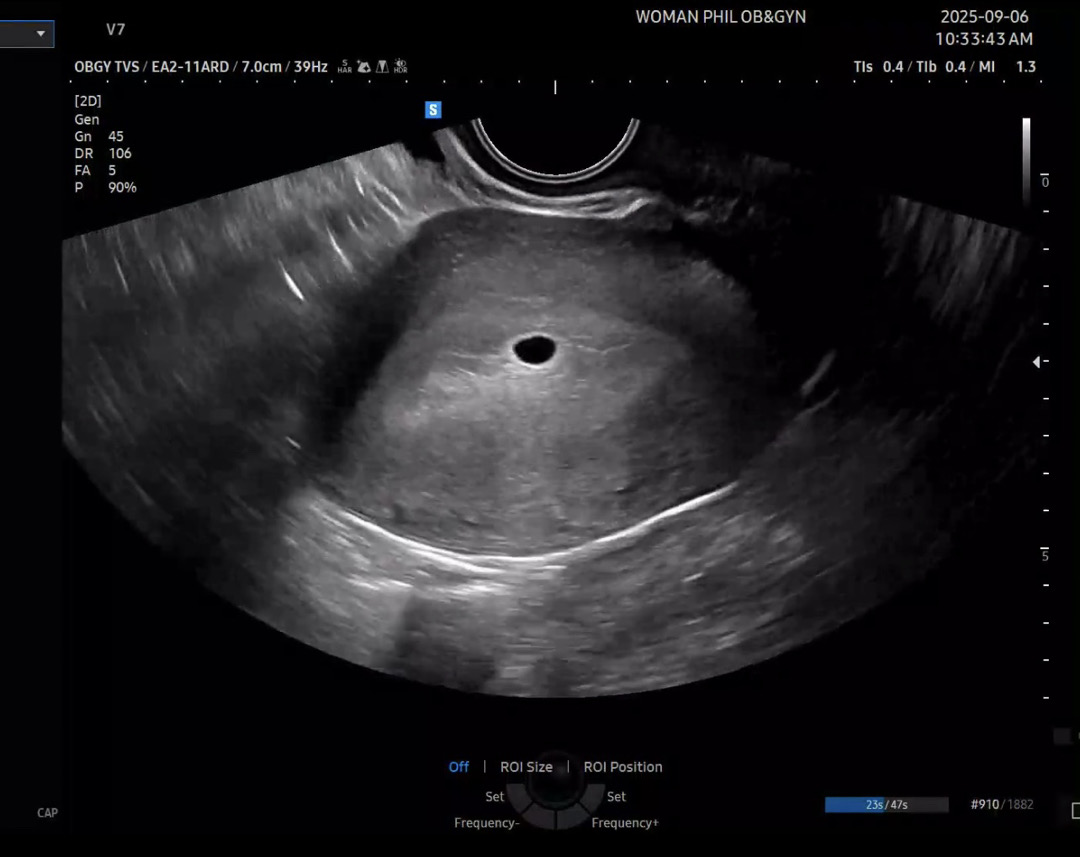

토요일날 5주0일 아기집 보고 왔는데 선생님께서 생각하신것보다 아기집이 작고 난황도 보일거라 생각했는데 안보인다고.. 이럴경우 유산될 확률이 높다고 말씀하셔서 걱정이네요ㅠㅠㅠ 제가 생리주기가 긴편이다보니 더 걱정되는 느낌이랄까요ㅠ

5주0일에 난황 보는 분이 별로 없을텐데 선생님이 너무 겁주셨네요ㅠㅠ 보통 아기집만 보인다고 하시는데.. 너무 걱정말고 기다려보세요 아직 주수가 너무 얼마 안됐어요

6주4일까진 기다려보세요! 저도 5주0일땐 난황도 안보였었어요